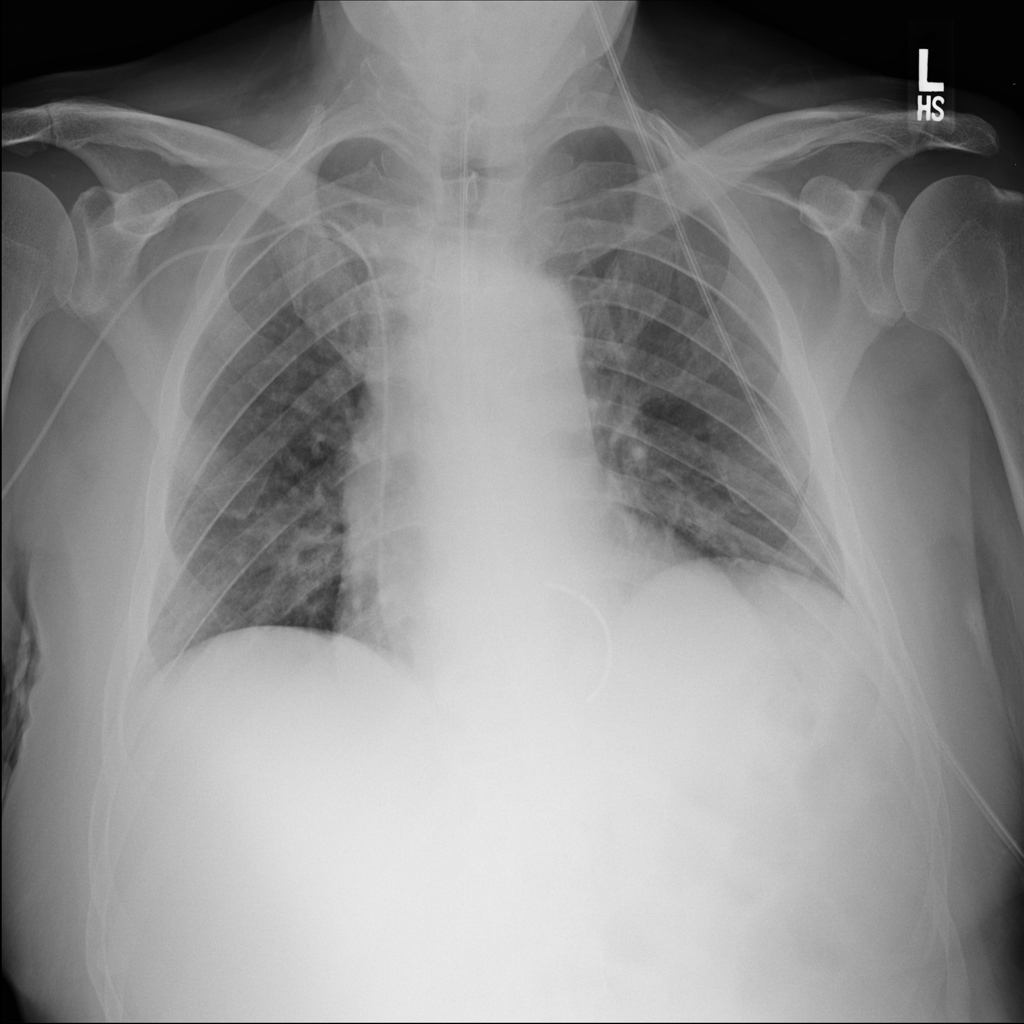

PAT-4F7E · IMG-000Hernia

PAT-4F7E · IMG-000

PA